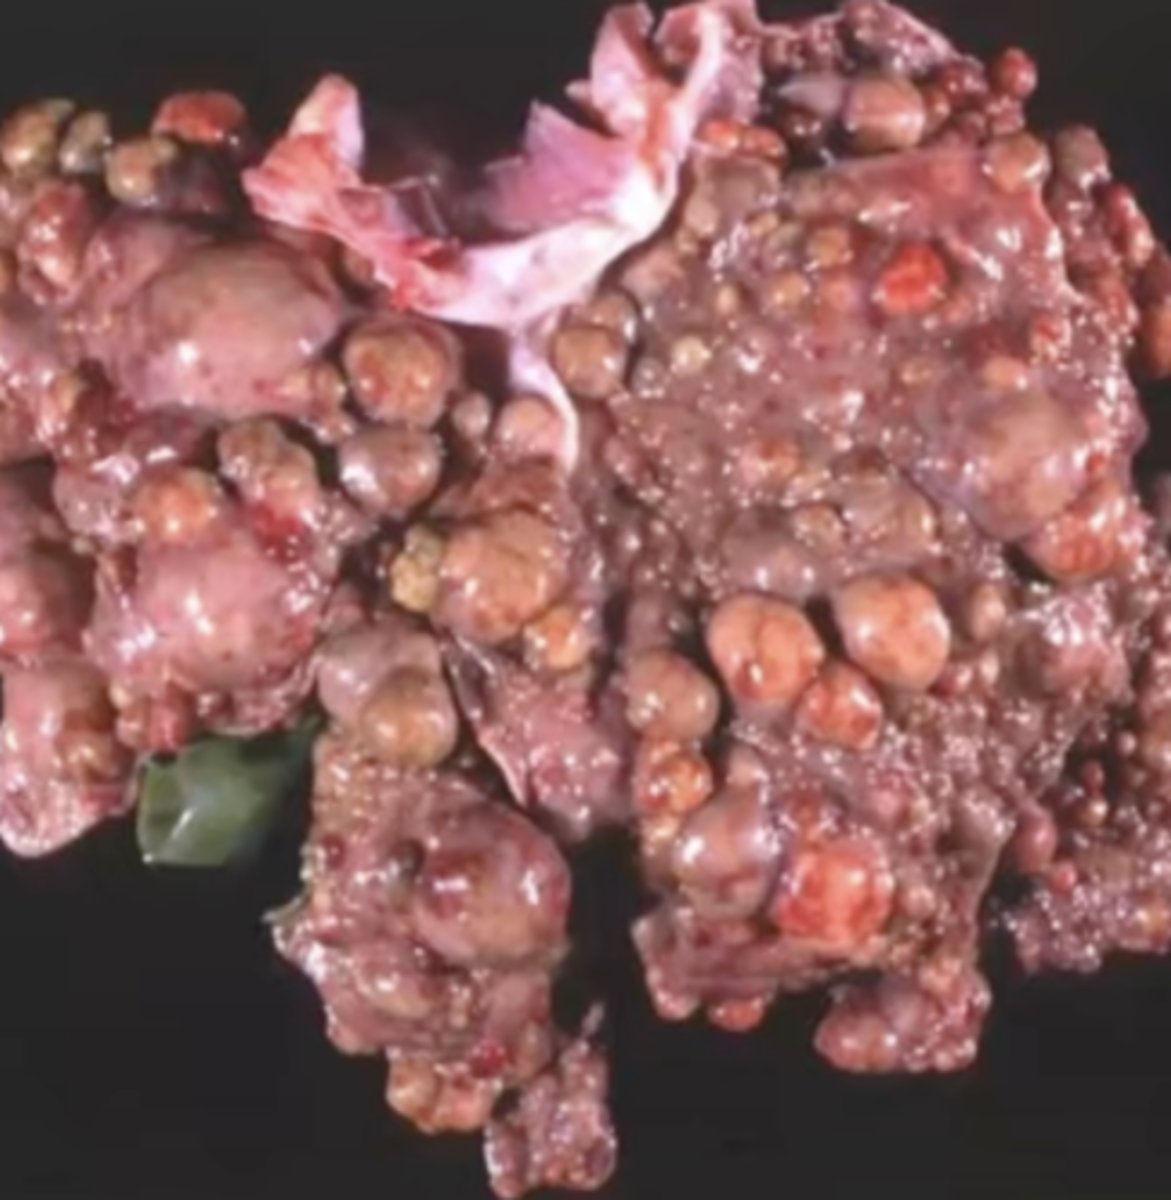

Hepatocellular carcinoma

-firm tissue

-malignant

-

What has caused this gross appearance of this liver?

Hepatocellular carcinoma

What has caused this gross appearance of this liver?

Hepatocellular carcinoma caused by a viral infection

What has caused this gross appearance of this liver?